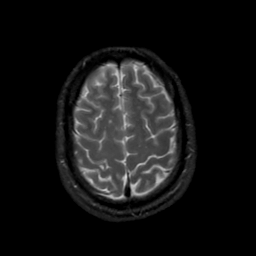

MR Study #20 October 6, 1991 -- Slice #41

[Home][Help][Clinical][Tour 1][Tour 2] Slice 41